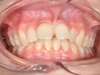

Cas 1 : Description

Après

Cas 2 : Description

Tendance prognathisme.Traitement par gouttières.

Avant